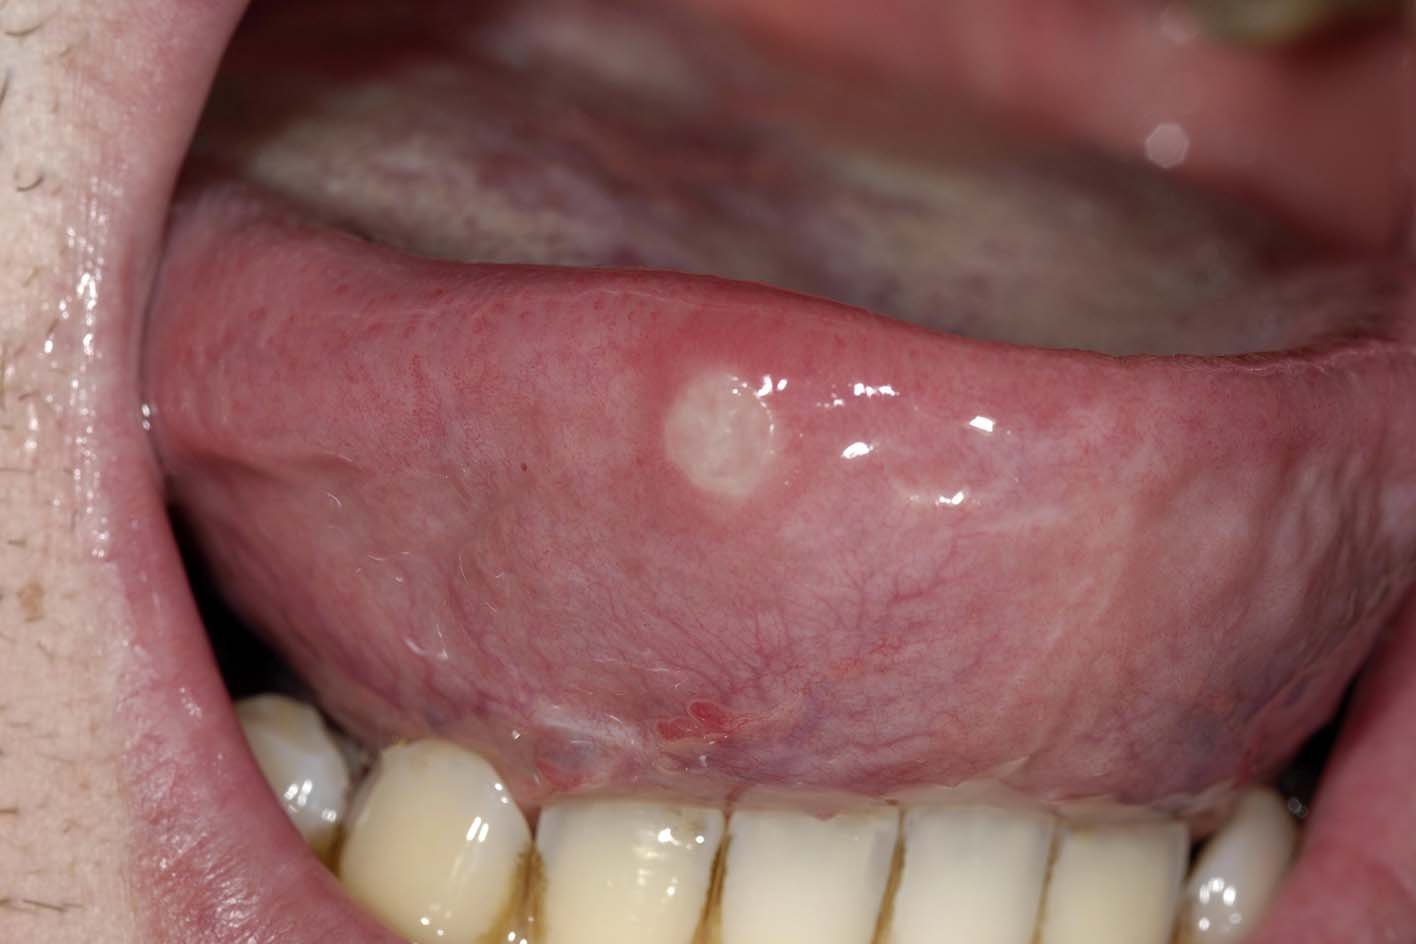

舌頭破(圖片來源:Canker Sore on Tongue)

舌頭破屬於口腔潰瘍的一種,形成原因並不單一,並非只是「火氣大」這麼簡單。從最常見的外傷、飲食刺激,到營養素缺乏、免疫力下降,甚至感染或潛在疾病,都可能讓舌頭黏膜變得脆弱,進而產生破洞。了解舌頭破洞原因,有助於你判斷嚴重程度與後續是否需要就醫。